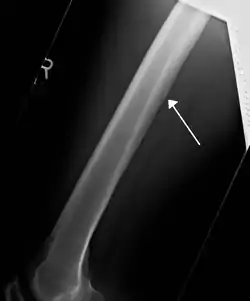

![]() A nutrient artery feeding the femur seen on X-ray | |